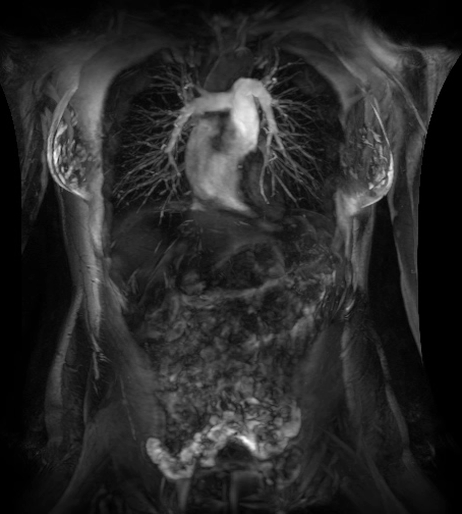

GE醫(yī)療全球在RSNA上展示了全面肝臟護(hù)理方案,可為肝臟疾病全路徑診治的每一步提供更精準(zhǔn)的信息。

在此次北美RSNA上,GE醫(yī)療全球展示了一系列推進(jìn)肝臟成像技術(shù)和開發(fā)的解決方案,從篩查、診斷和介入手術(shù)到治療計(jì)劃制定、療效評(píng)估,我們的全面肝臟護(hù)理產(chǎn)品組合可幫助放射科醫(yī)生根據(jù)患者年齡、病史、風(fēng)險(xiǎn)因素和個(gè)性化指標(biāo)提供更精準(zhǔn)、有效的治療;同時(shí)還能夠不斷改善患者體驗(yàn),簡化流程,增強(qiáng)臨床診治信心。

MR,早期肝臟健康(Resoundant)檢查

全面、定量、無輻射、快速(屏氣)和無創(chuàng)的肝臟評(píng)估。

定量評(píng)估甘油三酯脂肪濃度和R2 *(IDEAL IQ),肝臟組織硬度即時(shí)分析(MR Touch)??赡苡兄谠u(píng)估非酒精性脂肪性肝?。ㄖ荆?、脂肪性肝炎(炎癥)和肝硬化(纖維化)。致力于讓磁共振成像和活檢一樣精準(zhǔn)、有效。(待FDA 510K審批,未上市銷售)

LOGIQ E10,高級(jí)肝臟工具和自動(dòng)病變分割

LOGIQ?E10超聲波的下一代成像技術(shù)以及剪切波彈性成像、對(duì)比增強(qiáng)超聲和volume navigation等先進(jìn)工具使臨床醫(yī)生能夠診斷、治療和跟蹤各種狀況。自動(dòng)病變分割是一種人工智能工具,通過跟蹤病變邊界和相應(yīng)區(qū)域提供更豐富、精準(zhǔn)的診斷信息。